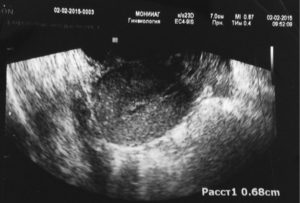

С такими признаками нужно срочно обращаться в клинику. Гинеколог назначит после осмотра ультразвуковое исследование, в ходе которого будет видно внутри осталась плацента или нет. Чтобы устранить последствия, проводится чистка под общим обезболиванием.

5 – 7 дней по окончании родовой деятельности выпадают сгустки крови. Затем они принимают мажущий характер и совсем исчезают. Если спустя 2 – 3 недели изменений не наблюдается, кровь продолжает вытекать, возможно, образовался полип. Когда плацента полностью не вышла после родов, УЗИ показывает увеличенную в размерах матку. Поэтому обильные выделения должны насторожить.

- Ультразвуковое исследование.

Если у вас продолжается обильное кровотечение в течение нескольких дней или недель после родов, вас направят на УЗИ чтобы выявить, не остались ли фрагменты плаценты в матке. Если подозрения подтвердятся, вас направят в больницу для хирургического удаления остатков плаценты из полости матки. Она проводится под анестезией и сопровождается введением антибиотиков.

Чистка матки проводится после родов, если в ней остались части плаценты или скопились сгустки крови. Обнаружить остатки можно на плановом ультразвуковом исследовании, которое проводят после родов.

Отличительной чертой данного заболевания является трудность в его диагностике, потому что начальная стадия приходится на послеродовые кровотечения, характерные для этого периода. Главной причиной полипов считается аборт или выскабливание в анамнезе. Обнаружить плацентарный полип можно только с помощью ультразвукового исследования.